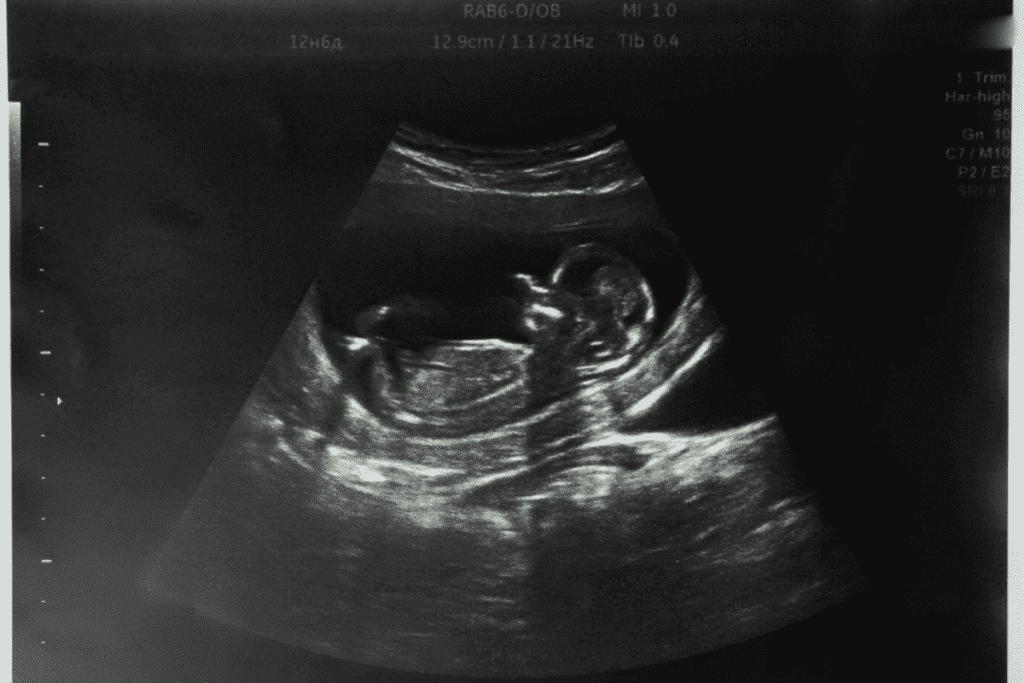

During the fifth week, the embryo’s major milestones include the formation of the neural tube. This will eventually develop into the brain and spinal cord. The heart begins to divide into chambers, and the foundations for the respiratory and digestive systems are established. The embryo is about 2-3 millimeters in length and is surrounded by a gestational sac, which is visible on an ultrasound.

By 5 weeks gestation, a transvaginal ultrasound can typically reveal a gestational sac. The embryo itself might be too small to detect. As the embryo grows, it will become more visible on subsequent ultrasounds.

What Can Be Seen on a 5-Week Ultrasound

A 5-week ultrasound is a big deal in pregnancy. It’s the first time you see the embryo growing. You can spot some important parts on the ultrasound, giving you key info about your pregnancy.

Gestational Sac Visualization

By 5 weeks, a gestational sac might show up on a transvaginal ultrasound. This sac is a key early sign of pregnancy. It looks like a small, fluid-filled area around the embryo.

The gestational sac’s visibility is a big sign that the pregnancy is moving along. But, you can’t see the embryo itself clearly yet.

Yolk Sac Identification

By 5 weeks, a yolk sac might start to show up inside the gestational sac. The yolk sac feeds the embryo early on, before the placenta is fully formed.

Seeing the yolk sac is a big deal. It shows the pregnancy is growing, even if it’s very early.

Fetal Pole and Cardiac Activity

By 5–6 weeks, you might see a fetal pole (the early embryo) and maybe even a heartbeat. The fetal pole is the embryo itself. Seeing a heartbeat is a good sign that the pregnancy is healthy.

Seeing cardiac activity is a key sign of the embryo’s health and if it’s viable.